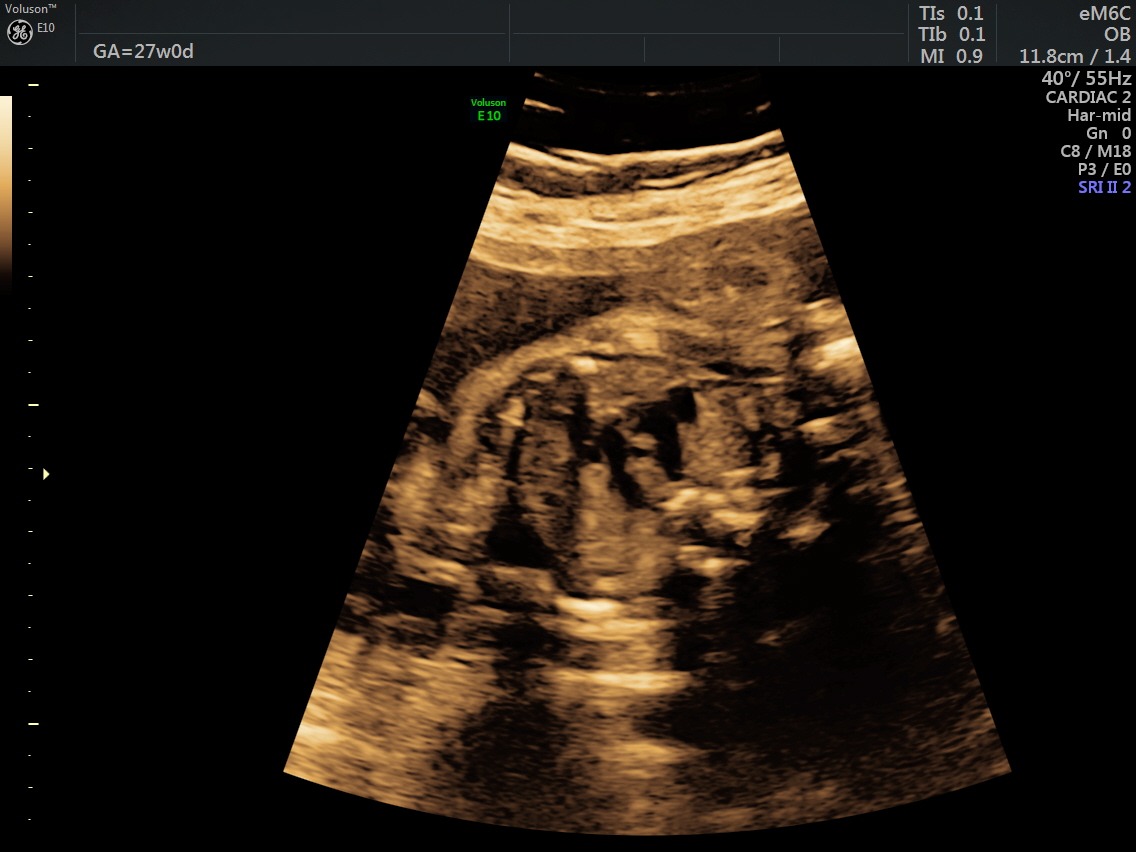

RT AORTIC ARCH_14 Published June 17, 2016 at 1136 × 852 in Rt aortic arch and aberrant left subclavian artery ← Previous Next →